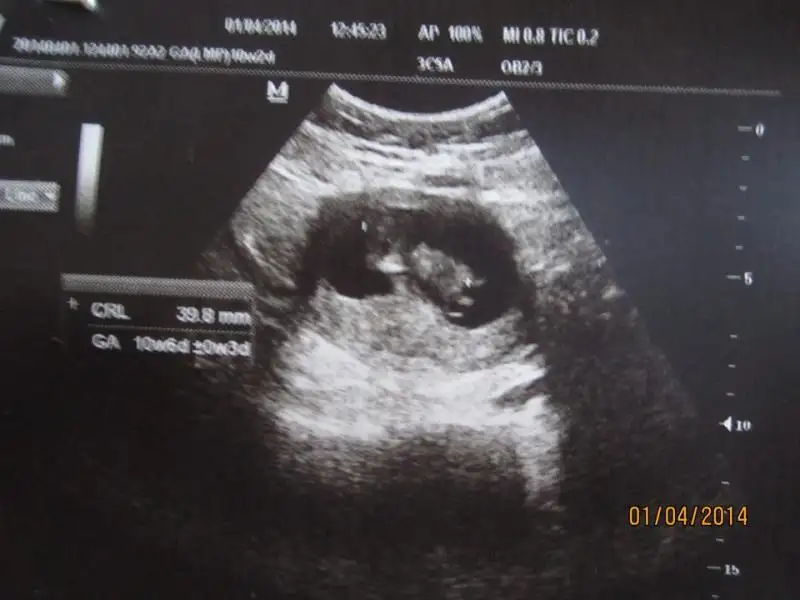

Eki Görüntüle 473837 bu benim kizim cikinti gayet net ve ortada ve ben kizim diyooo

10. haftamda genital cikintisi kiza isaret ediyordu tahmin etmistim ki dun kesinlesti

simdi nedir bu genital nub